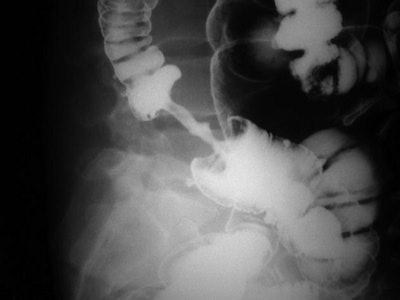

Apple core lesion: The annular carcinoma of the colon produces focal circumferential thickening of the bowel wall and narrowing of the colonic lumen, associated with shouldering. On a barium exam, the affected colon looks like a partially eaten apple.

Double-contrast barium enema shows apple core lesion due to carcinoma of colon.